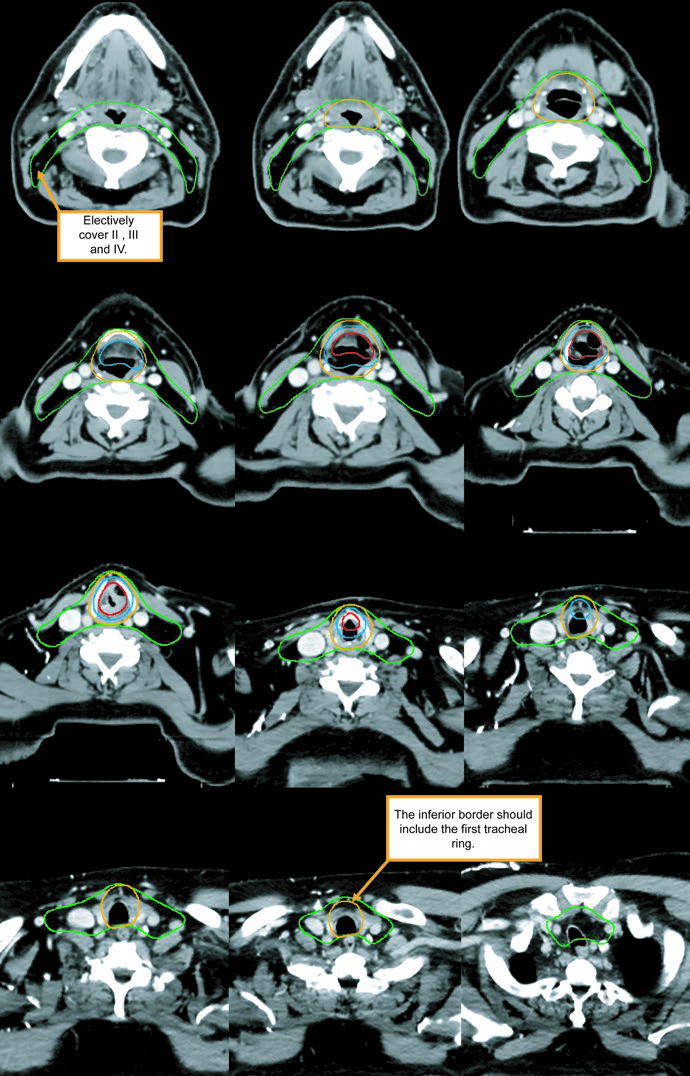

Advanced-stage disease: ≥T3 or node-positive

Once disease is T3 or higher, or the neck is involved, both necks belong in the plan. The preferred approach in the chapter is a sequential cone down: an initial 30-fraction plan delivers 54 Gy to low-risk subclinical disease and 60 Gy to high-risk subclinical disease, followed by 10 Gy in 5 more fractions to gross disease for a total of 70 Gy in 35 fractions. A single dose-painted IMRT plan is also acceptable, delivering 70 Gy, 63 Gy, and 54 Gy simultaneously over 35 days.

The subclinical primary CTV should cover the whole larynx from the bottom of the thyroid notch to the first tracheal ring, or farther inferiorly when needed. The subclinical nodal CTV should include at least levels II-IV and, in many cases, level VI. In the elective node-negative neck, the superior extent of level II stops where the posterior belly of the digastric crosses the internal jugular vein, corresponding to the caudal edge of the lateral process of C1. In the node-positive neck, level II should extend to the skull base and include the ipsilateral retrostyloid nodes.

| CTV 54-60a | Should encompass the entire GTV. Includes the entire larynx, from the bottom of the hyoid or the top of the thyroid notch to the bottom of the cricoid cartilage, with further inferior extension when needed. High-risk nodal regions include levels II-IV and the retrostyloid space on the involved node-positive neck. In the node-positive neck, level II should be treated to the base of skull. Level VI should be included if there is subglottic extension or a trach. |

| PTV 54-60a | CTV 54-60 + 3-5 mm, depending on immobilization, IGRT, and setup reproducibility. |

| CTV 54b | Levels II-IV of the uninvolved neck. In the node-negative neck, the superior border of level II stops where the posterior belly of the digastric crosses the internal jugular vein, or at the caudal edge of the lateral process of C1. Levels IB and V are not included unless there is gross disease at those levels. Retropharyngeal nodes may be covered at physician discretion on the side of bulky adenopathy because of retrograde flow. Level VII coverage is recommended for subglottic extension or hypopharyngeal involvement. |

| PTV 54b | CTV 54 + 3-5 mm, depending on immobilization, daily localization, and related treatment factors. |

Subclinical disease may be contoured as one CTV or as two CTVs divided into high-risk and low-risk regions.

a High-risk subclinical dose: 1.8-2 Gy per fraction to 54-60 Gy. b Low-risk subclinical dose: 1.54-1.8 Gy per fraction to 54 Gy.

Levels IB and V are not elective by default and are only included when gross disease is present there. Retropharyngeal nodes may be covered on the side of bulky adenopathy at physician discretion. Level VII is recommended for subglottic extension or hypopharyngeal involvement. That is one of the most useful parts of the chapter because it turns abstract spread patterns into concrete cranial and caudal borders.

The figure caption adds two good reminders. In that example, level IB was included by the treating physician even though it can be omitted. The upper trachea was not treated, but the text notes that it should be included when indicated. That is a useful warning against copying a figure without rechecking the anatomy.